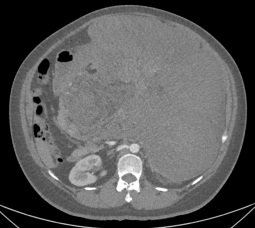

经进一步检查,患者小吴腹膜后及腹腔内藏着一个巨大的肿块,主体主要位于左中上腹,向下达盆腔入口,较大层面横切面约31.4×28.4cm,肿块推挤腹腔脏器,胰腺、胃、十二指肠向右前移位,脾脏向上移位,左肾向后移位,相应结构受压稍变形,胰腺部分显示不清,部分病灶包绕左肾及左肾上腺;病灶推挤肠管,部分与肠管分界不清。

(腹膜后及腹腔巨大肿物)